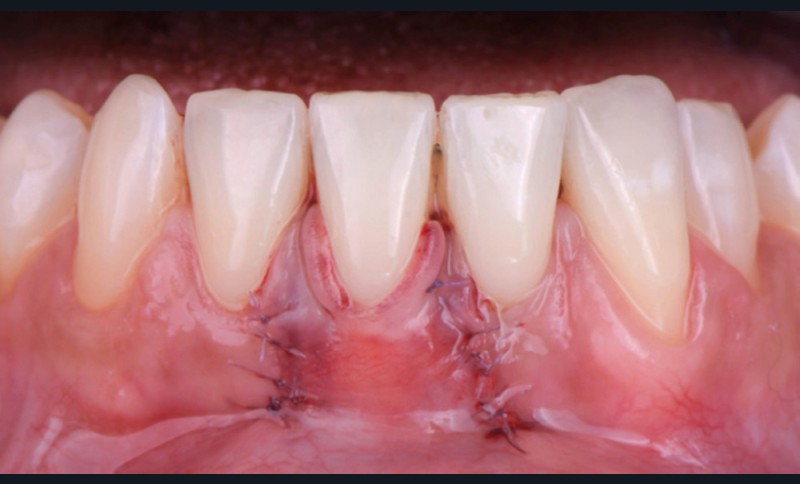

Le lambeau positionné coronairement associé à une greffe de conjonctif enfoui (fig. 1-4)

La stabilité du lambeau est primordiale dans la réussite de cette technique de recouvrement. En cas d’instabilité, même en l’absence d’erreurs techniques, l’analyse de certains facteurs liés au patient est indispensable. Afin de maintenir la stabilité du lambeau jusqu’à la dépose des points, le praticien doit veiller à l’adéquation du contrôle de plaque effectué par le patient, à l’absence de mastication impliquant la zone d’intervention, à la prévention de tout traumatisme ou de modifications des conditions locales par le patient.

Selon le Dr Sylvie Pereira, contrairement au maxillaire où la hauteur du lambeau déplacé coronairement est déterminée par la profondeur de la récession, à la mandibule, les incisions horizontales sont placées de manière à obtenir au moins 2 mm de tissu…